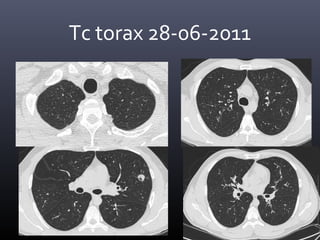

Tc torax 28-06-2011

• CONCLUSION TOMOGRAFICA:

• Nódulo pulmonar cavitado en el segmento 4 izquierdo con

afección de parénquima adyacente, lo cual como primera

posibilidad corresponde a Tuberculosis y diagnostico

diferencial de Coccidiodiomicosis.